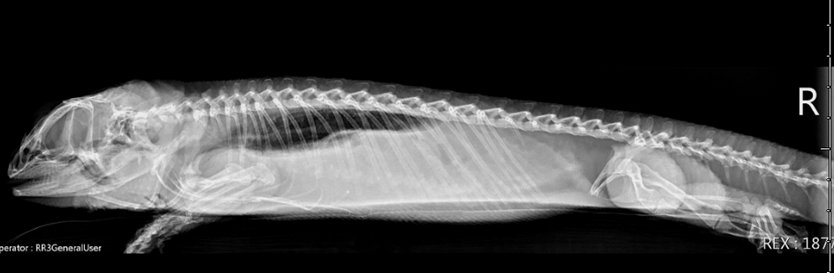

A complete blood count was performed revealing toxic changes (toxic granules) within the heterophils with a normal total white blood cell count and normal packed cell volume. Blood chemistry revealed elevated creatinine kinase (CK 2575 U/L)) and hyperglycemia (399 mg/dL). Initial diagnostics also included whole body radiographs (Figure 3a and b) to evaluate bone density and look for any other potential foreign material. The radiologist report confirmed normal bone density and no radiopaque foreign material. The lung fields were noted to be asymmetric, likely due to atelectasis. Due to the reported hyperglycemia and persistent firm material palpable in the coelom, the patient later had a coelomic ultrasound performed. Results were consistent with desiccated fecal material and gastrointestinal dilation consistent with functional ileus.

Figure 3b – Lateral view (horizontal beam)